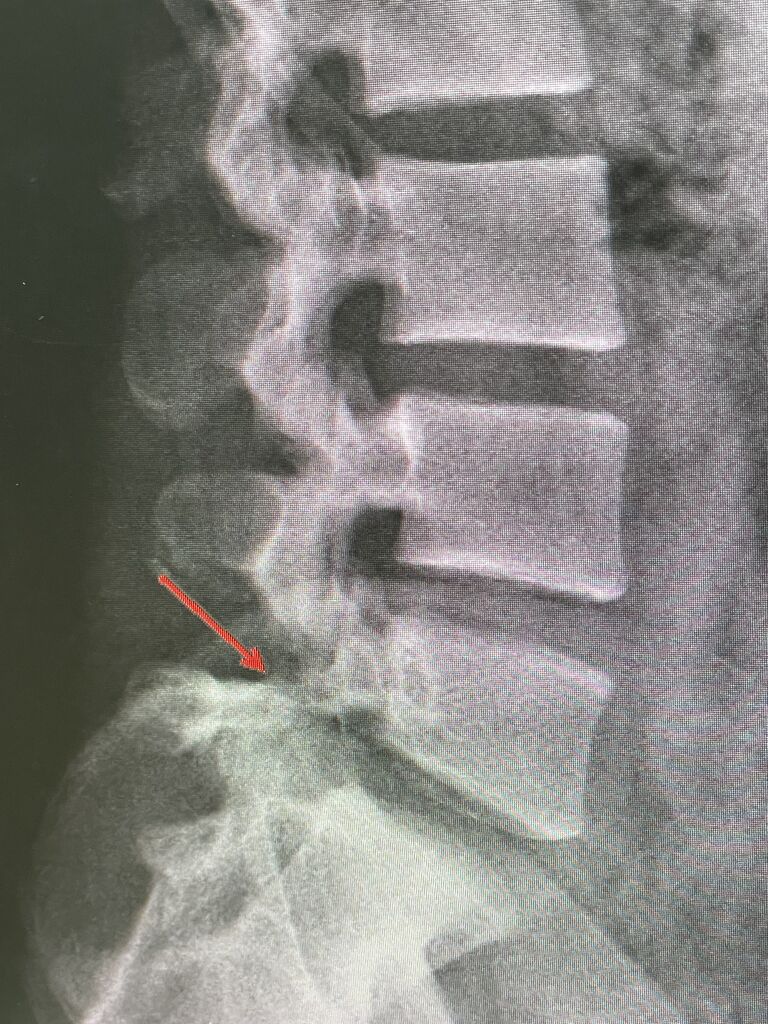

腰の痛みが続き、MRIにて、

脊柱管狭窄症がありますが、

L5 /S1の椎間板だけ、正常な特殊な腰でした、

ストレッチ、筋肉トレーニング、

立体動態波、微弱電流で

良くなっていくと思います